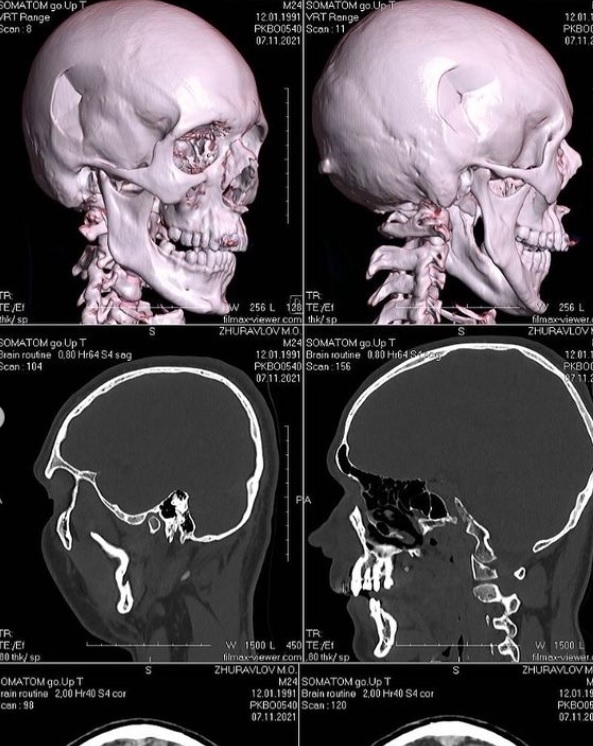

Я був побитий у своєму під'їзді. Хірург сказав, що з такими травмами зазвичай до лікарні приїжджають у комі. Але ми з Діаною (його дівчина. - Ред.) ще 12 годин після травми їздили по всьому Києву робили обстеження, комп'ютерну томографію та інше, - написав він.

Журавльов написав, що у нього діагностували перелом черепа та носа. Також він став погано бачити на одне око.

Кілька годин тому пройшла операція з видалення пошкоджених кісток черепа. Через місяць потрібна операція щодо впровадження в голову пластини, - додав музикант.